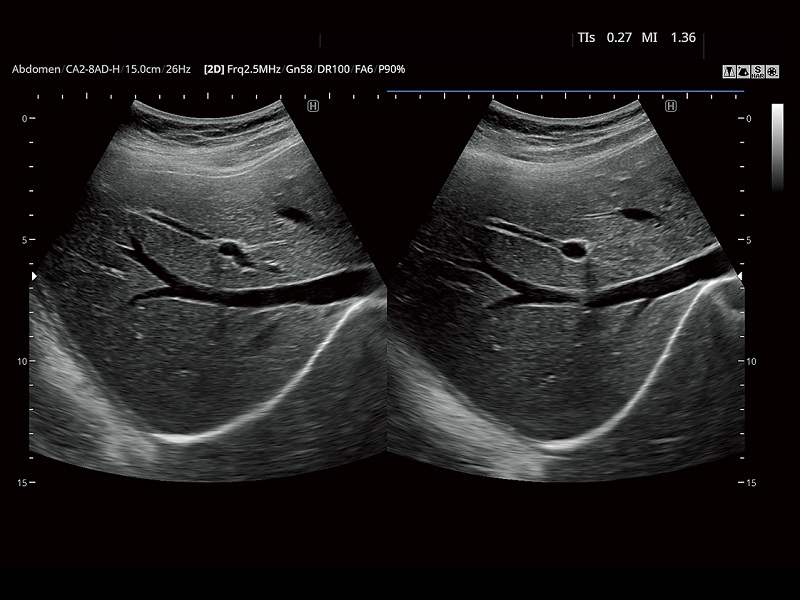

FUTUS features great imaging technologies to support a clear view and confident diagnoses.